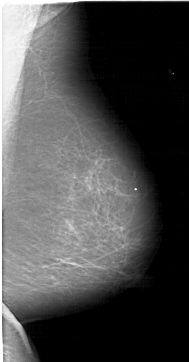

A_1513_1.RIGHT_CC

RIGHT_CC LINES 6286 PIXELS_PER_LINE 3301 BITS_PER_PIXEL 12 RESOLUTION 43.5 NON_OVERLAY